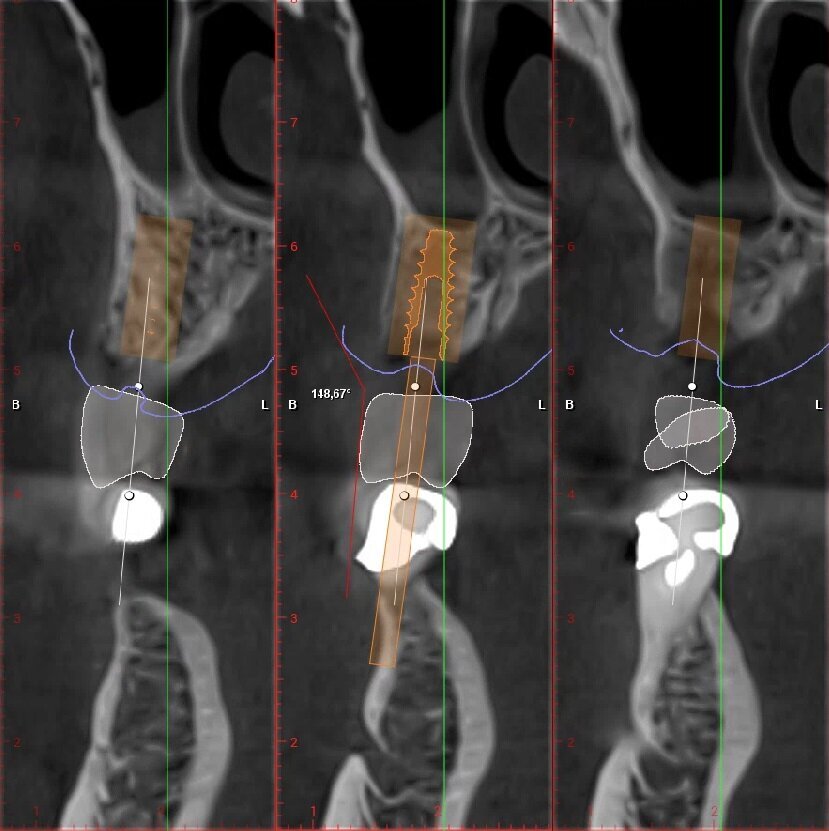

Posizionamento protesicamente guidato dell’impianto, tenendo conto dello spessore dei tessuti molli; che idealmente dovrebbe essere intorno ai 2-3 mm. Con valori più alti di 3-4 mm è indicata una ricostruzione ossea verticale al fine di riportarne la lunghezza in un range di normalità (Figg. 6, 7).

_Valutazione dell’angolo di emergenza della protesi (angolo di detergibilità)

L’angolo formato tra la protesi e la cresta alveolare dovrebbe essere maggiore di 130°, un valore più acuto può creare accumulo e ristagno di cibo nella porzione apicale della protesi, causando difficoltà di mantenimento igienico13. Qualora il valore fosse minore, sarebbe indicata anche una ricostruzione ossea orizzontale (Figg. 8, 9). Particolare attenzione andrebbe, inoltre, mostrata alla posizione del processo zigomatico del mascellare superiore: una sua inserzione molto crestale creerebbe importanti difficoltà non solo nell’esecuzione di una procedura rigenerativa extra-sinusale, ma specialmente in seconda fase chirurgica dove andare a ricreare una adeguata profondità di fornice sarebbe molto complesso.

Fig. 6_Pianificazione implantare protesicamente guidata dell’elemento 2.5.

Fig. 7_Pianificazione implantare protesicamente guidata dell’elemento 2.6.

Fig. 8_Valutazione angolo di emergenza della protesi elemento 2.5, valore 148,67°..

Fig. 9_Valutazione angolo di emergenza della protesi elemento 2.6, valore 152,43°.